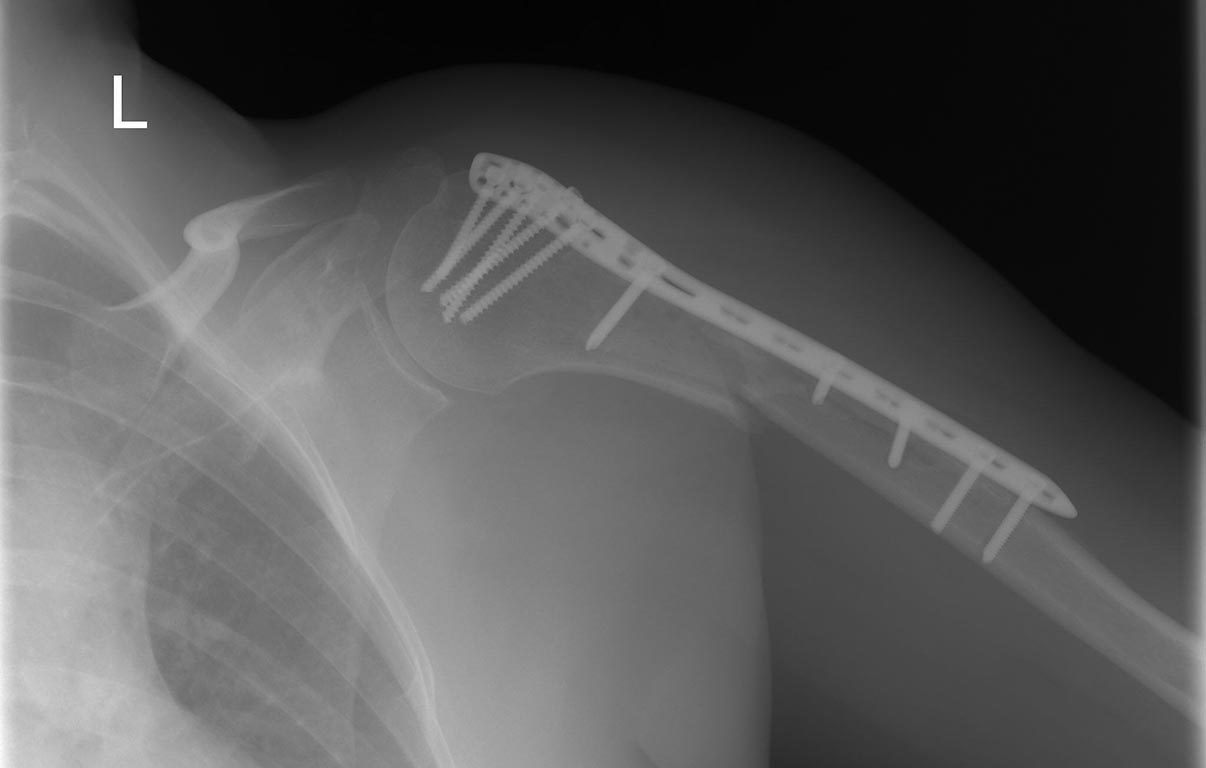

Нестабильность остеосинтеза, несращение перелома плечевой кости.

Пациент С 1959 г.р. В конце февраля 2015 г. поступила в клинику с закрытым оскольчатым спиральным переломом в/3 плечевой кости.

Было принято решение оперативное лечение осуществлять накостным остеосинтезом из-за промежуточного отломка, к которому крепилось сухожилие большой грудной мышцы. Нашли самую длинную подходящюю пластину, во время операции остеосинтез был стабильный, хоть и пластина коротковата:((. Больной после операции сразу же разрешили активные движения в локтевом и плечевом суставе. Как она реабилитировалась амбулаторно неизвестно.

На контрольной явке через 3 месяца имеется картина нестабильности остеосинтеза и несращения перелома.

Что можете посоветовать по дальнейшей тактике? Мое решение на данный момент-удаление металлофиксатора и БИОС с рассверливанием костного канала.